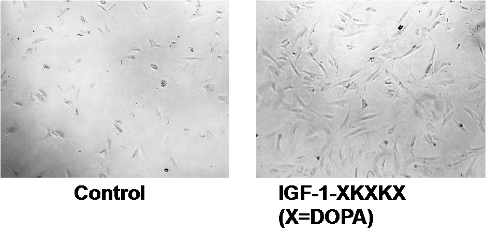

According to Chen Zhang of the RIKEN Nano Medical Engineering Laboratory, the first author of the paper published in Angewandte Chemie, “We thought it would be interesting to try to use various techniques to attach a biologically active protein—in our case we chose insulin-like growth factor-1, a promoter of cell proliferation—to a titanium surface like those used in implants” (Figure 2).

Using a combination of recombinant DNA technology and treatment with tyrosinase, they were able to create a hybrid protein that contained active parts of both the growth factor and L-DOPA. Tests showed that the proteins were able to fold normally, and further experiments in cell cultures demonstrated that the IGF-1 was still functioning normally. Thanks to the incorporation of the L-DOPA, the team was able to confirm that the proteins bound strongly to the titanium surface, and remained attached even when the metal was washed with phosphate-buffered saline, a water-based solution. Zhang says, “This is similar to the powerful properties of mussel adhesive, which can remain fixed to metallic materials even underwater.”

Cell growth enhancement with bound IGF titanium